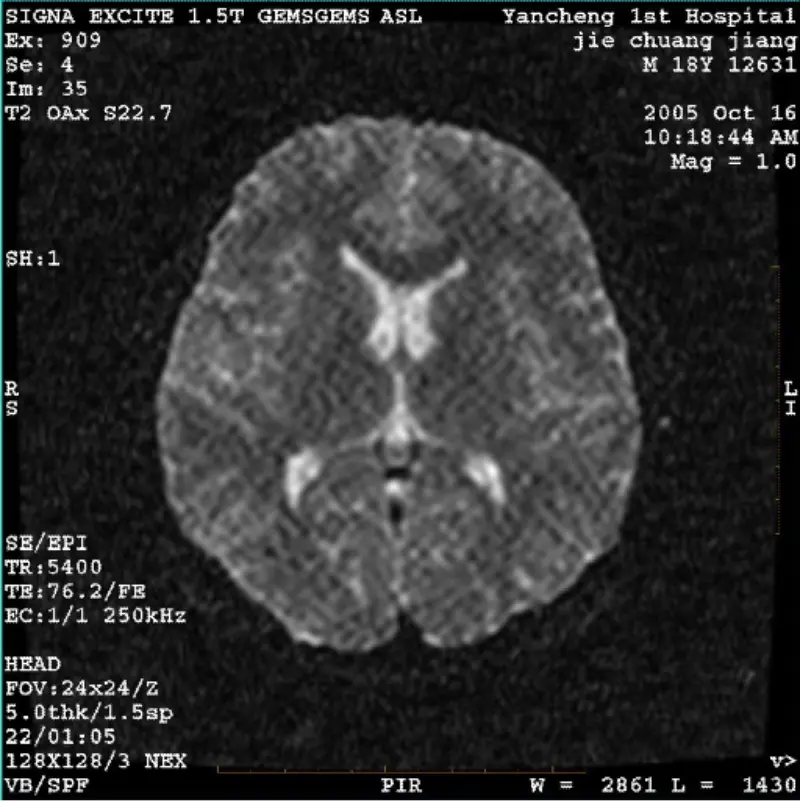

Baca selengkapnyaSISTEM: 1.5T Signa Twin Excite II (Versi Perangkat Lunak 11.0M4) MASALAH/Gejala DWI (Mode zoom dan mode keseluruhan) dan pesta (mode zoom dan mode keseluruhan) memiliki gambar artefak retikulat atau korduroi yang terlihat tidak peduli saat menggunakan body coil atau head koil, gambar rutin la......